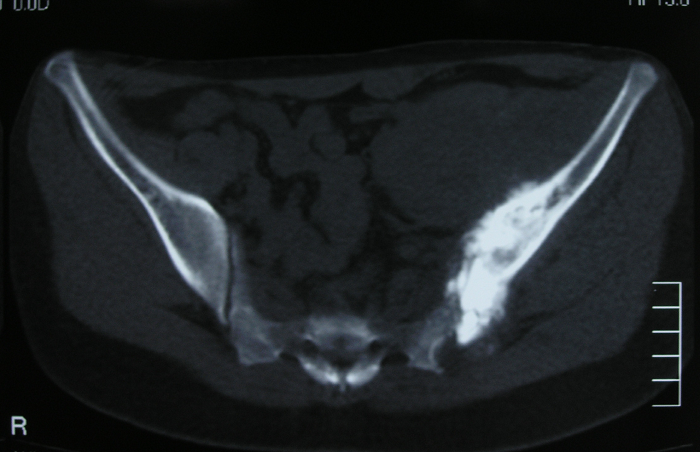

6、病例6:女 18岁 左半骨盆骨肉瘤,全身及肿瘤局部选择性动脉灌注大剂量化疗后行肿瘤切除人工半骨盆假体置换术

图 33 术前X线片

图 34、35、36 术前CT:肿瘤体积巨大,压迫

输尿管、膀胱等盆腔脏器

图 37 术前MRI

图 38 术前ECT

图 39 术前DSA

图 40 术前动脉化疗装置

图 41 肿瘤标本

a:外观象 b:剖面象

图 42 术后X线片